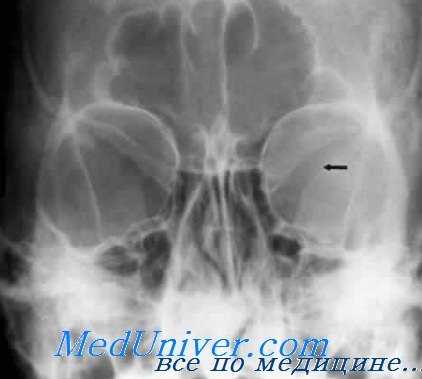

УКЛАДКИ СНИМОК ГЛАЗНИЦЫ В НОСОПОДБОРОДОЧНОЙ ПРОЕКЦИИ

Назначение снимка. Изучение состояния костей, образующих вход в глазницу, костной структуры верхней и наружной ее стенок.

Укладка больного для выполнения снимка сходна с укладкой для выполнения обзорного снимка в этой же проекции. В данном случае используюткассету размером 13X18 см, располагая ее в кассетодержателе в поперечном положении. Больной прилежит к столу подбородком и кончиком носа,переносье соответствует центру кассеты. Центральный пучок излучениянаправляют на центр кассеты. Фокусное расстояние—100 см.

В этой же укладке может быть выполнен снимок одной (правой или левой) глазницы. В таких случаях центр снимаемой глазницы соответствует центру кассеты, и на него отвесно направляют пучок излучения, используя тубус или диафрагмирование пучка излучения с помощью щелевой диафрагмы. Фокусное расстояние—100 см (рис. 88).

Информативность снимка. На снимке хорошо видны вход в глазницу, структура ее стенок, иногда малое и большое крыло клиновидной кости (рис. 89). На снимке в этой проекции могут быть выявлены деструктивные изменения стенок глазницы и инородные тела в ее полости (рис. 90, 91). Для выявления изменений в области верхней стенки глазницы (например, при

диагностике переломов) снимок целесообразно выполнять не в носоподбородочной, а в подбородочной проекции.

На таких снимках верхняя стенка глазницы проекционно искажается в меньшей степени, и все изменения в ее области видны более отчетливо (см. рис. 54, 55).

На прицельном снимке каждой из глазниц в этой же проекции, как правило, небольшие изменения структуры стенок, а также мелкие инородные тела глаза видны лучше. Такие снимки широко используют в офтальмологической практике (рис. 92).

Критерии правильности технических условий съемки и правильности укладки основываются на четкости выявления костной структуры и симметричности изображения глазниц.

Наиболее частые ошибки при выполнении снимка сводятся к асимметрии положения головы.